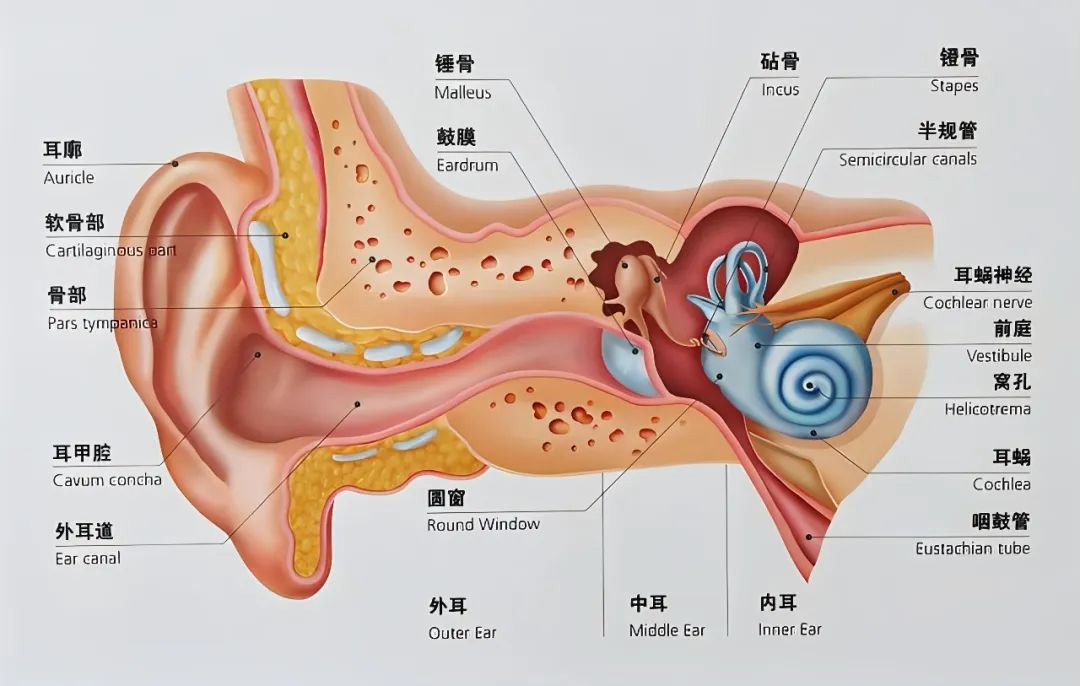

除了噪音,耳部感染也是一大“杀手”。棉签掏耳划伤耳道、游泳时耳部进水、感冒引发的中耳炎等,若不及时治疗,可能会导致鼓膜穿孔、听力减退。老年人更是耳部疾病的高发群体,随着年龄增长,内耳功能退化,像老年性耳聋的发病率逐年攀升,极大地影响了他们的社交与生活质量,让晚年的沟通交流变得困难重重。

科室配备了先进的听力检测设备,如纯音测听仪、声导抗仪等,能够全方位、高精度地评估耳部功能,精准捕捉听力细微变化,为疾病诊断提供可靠依据。在治疗手段上,我们紧跟医学前沿,开展了微创鼓室成形术治疗中耳炎,最大限度保留耳部结构与功能;针对突发性耳聋,采用个性化的综合治疗方案,争分夺秒挽救听力。